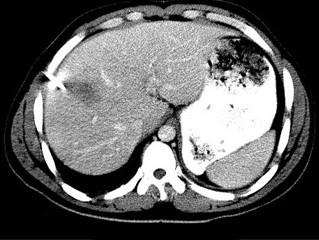

下列图像的最佳诊断是 ( )A.阿米巴肝脓肿B.原发性肝癌C.肝硬化D.脂肪肝E.肝囊肿

问题 下列图像的最佳诊断是 ( )

选项 A.阿米巴肝脓肿 B.原发性肝癌 C.肝硬化 D.脂肪肝 E.肝囊肿

答案 A